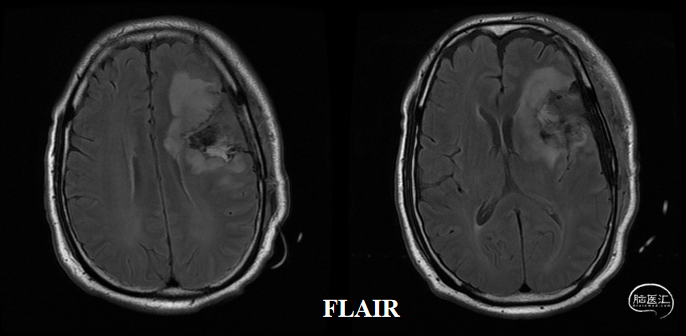

术前核磁(2020-03),左侧额岛叶肿块,信号不均匀,其内可见出血和坏死,占位效应明显,周围见水肿:图示。

术后48小时MR,可见左额不规则混杂信号影,周围水肿:图示。

肿瘤电场治疗16天,RT后1月(2020-07-22):图示。

术后5周开始实施标准的新STUPP方案的辅助治疗,即在同步放化疗后,辅助替莫唑胺化疗的同时使用了电场治疗。目前生存25月,且临床和影像学表现均提示稳定,未见复发迹象。期间,在放疗后7月时复查MRI提示异常FLAIR信号区增大,经我院MDT讨论,考虑到强化信号减轻,无明显占位效应,患者无症状体征,考虑是治疗后水肿,非进展,故继续按原方案治疗。放疗后17月复查MRI出现术区边缘局部强化范围稍增大,但PWI示强化区局部呈低灌注且未见弥散受限表现,MDT讨论考虑为假性进展,继续原方案治疗。后续复查MRI强化范围减轻,证实了MDT的判断证实疾病稳定。患者生存时间已达25个月。全程安全顺利,仅出现一过性轻度皮肤反应。

入院前头MRI(2020-3):左侧额岛叶肿块,信号不均匀,其内可见出血和坏死,占位效应明显,周围见水肿。考虑左额岛叶肿瘤(高级别脑胶质瘤可能性大)。于2020年4月行左额岛叶占位性病变切除术。术中见肿瘤组织位于左侧额中回及额下回后部,大小约4m×5cm×5cm,呈烂鱼肉样,色灰红,质软,部分坏死,血运中等,边界不清,侵犯左侧岛叶向下挤压颞叶。显微镜下沿肿瘤周边胶质增生带完整切除肿瘤。术后48小时内复查头MRI平扫、加强,影像显示术腔边缘不规则线样强化,靠近放射冠及侧脑室壁强化明显,可疑少许残存。